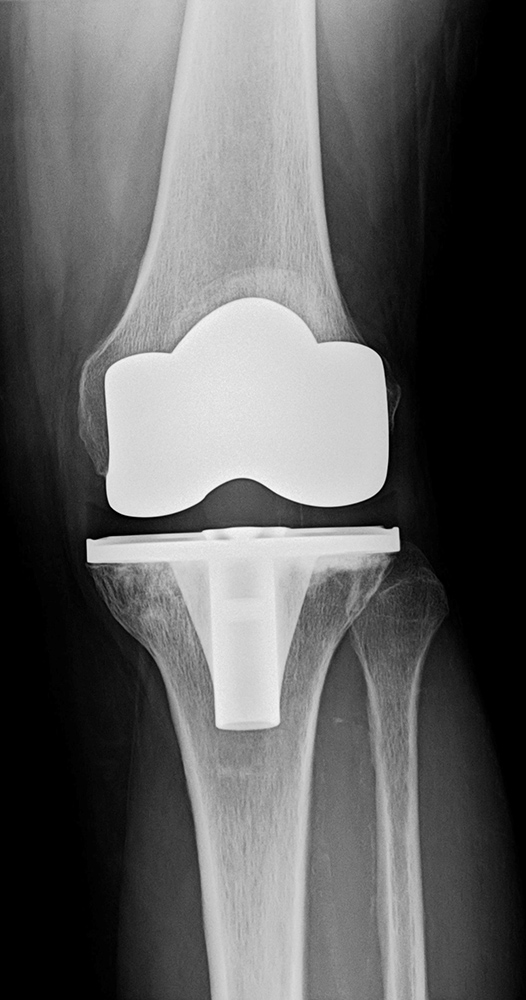

傷んだ関節表面を人工関節の形に合わせて削り、金属、セラミック、ポリエチレンでできた人工関節を骨の上に固定します。人工関節の耐久性は10年間弛みなく日常生活が送れる可能性が95%以上といわれ、長期的にも安定した方法です。

TKAの術後

関節のなかで傷んだ部分だけ(多くは内側の半分だけ)を人工関節に置換します。

メリットは手術の傷や削る骨の量が少ないため、術後の痛みも少なく、回復が早く、膝の曲がりもよいところです。耐久性も悪くありませんが、人工膝関節全置換術と比べると若干手技が難しく、適応をしっかり選ぶ必要があります。